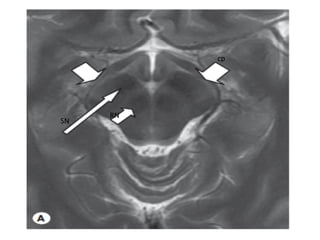

cp

SN

RN

•  Midbrain

•  Ventral: Cerebral peduncles (crus cerebri) containing

corticospinal, corticobulbar and corticopontine tracts

•  Dorsal tegmentum: Ventral to cerebral aqueduct

Gray matter: Substantia nigra and red nucleus

Upper midbrain: Contains CN3 nucleus, at superior

colliculus level

Lower midbrain: Contains CN4 nucleus, at inferior

Tectum (quadrigeminal plate): Dorsal to cerebral aqueduct

• Superior & inferior colliculi

• Periaqueductal gray matter

fourth cranial nerve, the only cranial nerve, exits from the dorsal aspect of the

brain stem

*CN3 susceptible to compression by PCA

aneurysms and uncal herniation